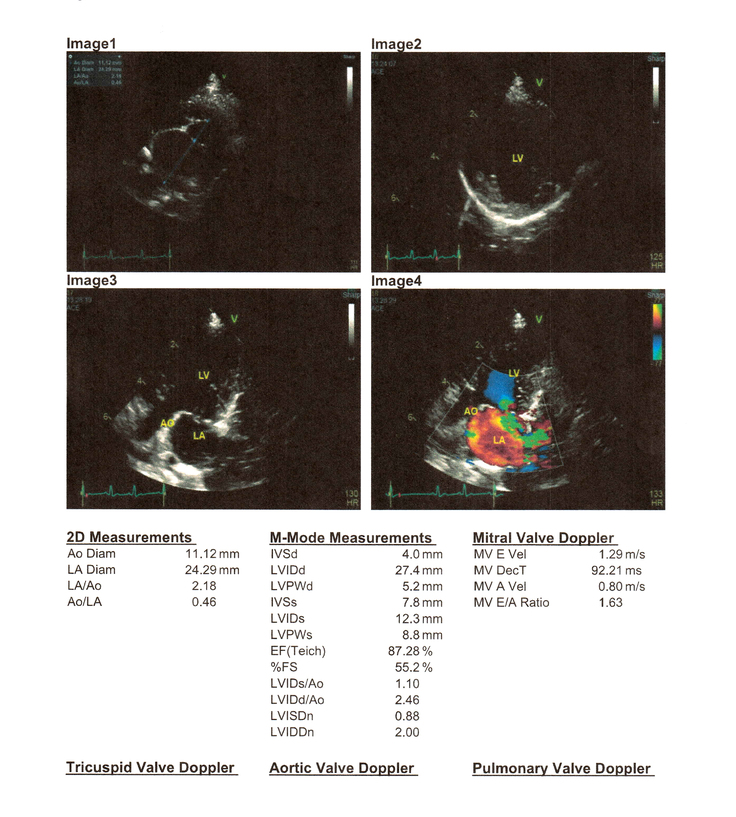

エコー画像を見ても、結石や「つまり」がハッキリと見てとれました。